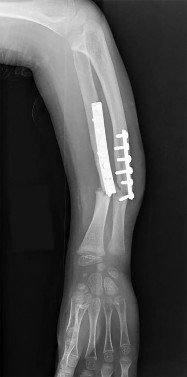

Question 32

An 8-year-old, 35 kg boy sustains a transverse midshaft fracture of the right femur. He is treated with titanium elastic nails (TENs). What is the most common complication associated with this surgical treatment?

Question 47

A 3-year-old boy sustains an isolated midshaft femur fracture. Radiographs demonstrate 1.5 cm of shortening and 10 degrees of varus angulation. What is the most appropriate definitive management?